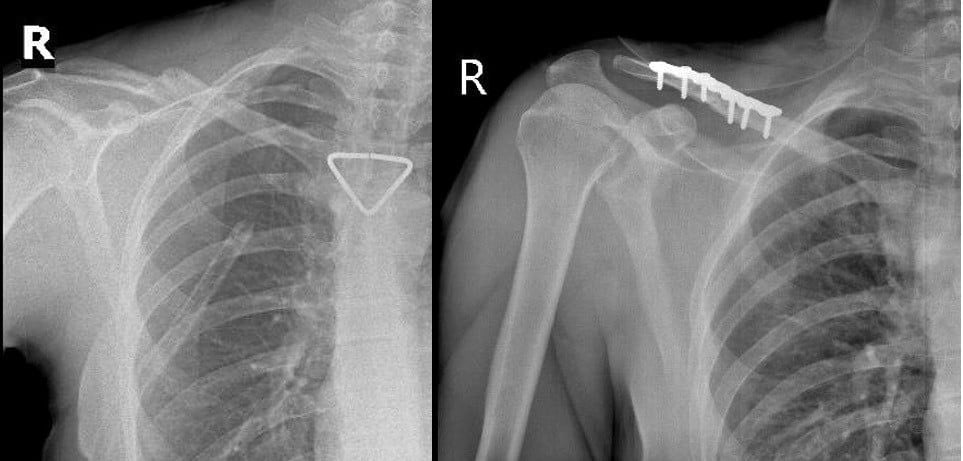

Qua hội chẩn liên chuyên khoa và đánh giá của bác sĩ gây mê hồi sức, người bệnh đủ điều kiện an toàn để thực hiện phẫu thuật kết hợp xương đòn phải bằng nẹp vít. Ca mổ do ê-kíp BSCKII Trần Văn Dương và BS Phạm Ngọc Huy thực hiện, diễn ra thuận lợi. Nẹp vít được đặt vững chắc, trục xương phục hồi giải phẫu tốt.

Hình ảnh Xquang trước và sau mổ. Nẹp vít được đặt vững chắc, trục xương phục hồi giải phẫu tốt

Sau phẫu thuật, người bệnh hồi phục nhanh, vận động tay phải cải thiện từng ngày và xuất viện sau 4 ngày điều trị tại khoa trong tình trạng sức khỏe ổn định.